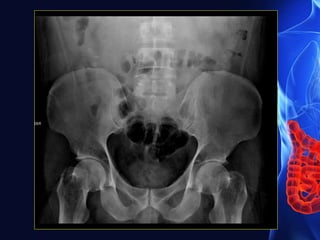

Signs of acute appendicitis in plain film

• Appendix calculus (0.5-6 cm)

• Sentinel loop-dilated atonic ileum containing a fluid level

• Dilated caecum

• Widening of the properitoneal fat line

• Blurring of the properitoneal fat line

• Right lower quadrant haze due to fluid and oedema

• Scoliosis concave to the right

• Right lower quadrant mass indenting the caecum

• Blurring of the right psoas outline-unreliable

• Gas in the appendix-rare, unreliable